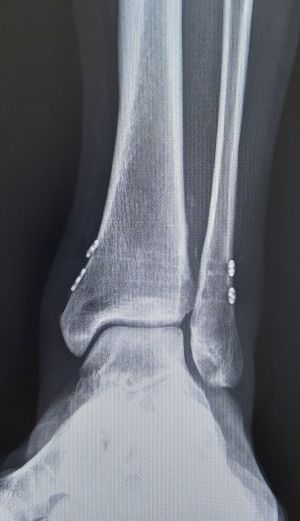

Eine operative Therapie ist bei anhaltenden Schmerzen trotz konservativer Therapie und gegebenem Leidensdruck angeraten. In Fällen, wo eine solche nicht erwünscht oder nicht durchgeführt werden kann, bleibt noch eine dauerhafte orthopädische Schuhversorgung. Im Falle einer Operation wird meist eine Arthrodese (Versteifung) des oberen Sprunggelenkes durchgeführt. Je nach Indikation kann dies entweder mittels gekreuzter Schrauben oder mittels Platten durchgeführt werden, bei Arthrose auch des unteren Sprunggelenkes, kann ggfs. eine Versteifung mit einem Nagel erfolgen. Alternativ bleibt noch die Möglichkeit eines Gelenkersatzes also die Implantation einer Endoprothese. Die Prothesen im Bereich des OSG haben allerdings noch nicht die Haltbarkeit, wie wir sie von Prothesen des Hüft- und Kniegelenkes kennen.

Es erfolgt eine operative Therapie mit Reposition des Wadenbeines und Halten durch Stellschrauben oder speziellen Implantaten (TightRope®). Die Nachbehandlung besteht in einer 6 wöchigen Gipsruhigstellung. Bei Einbringung von Schrauben, werden diese nach etwa 6 Wochen entfernt.